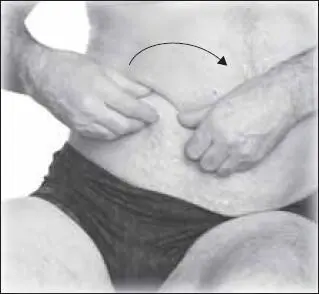

Затем следует перейти к приемам классического массажа. Начнем с щипцеобразного разминания нижней части живота, двигаясь по часовой стрелке (справа налево) (рис. 132).